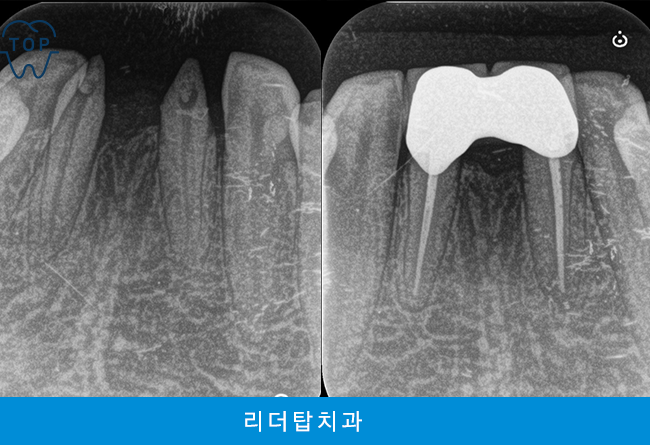

오늘은 가정동치과에서 아래쪽에 남아 있는 유치를 발치하고 브릿지를 진행하신 환자분을 소개해 드리도록 하겠습니다.

환자분께서는 아래 앞니에 유치가 빠지지 않고 남아 있어 보기 싫은데 뽑고 나서의 치료 방법 상담을 위해 내원해 주셨는데요. 다른 치아들은 모두 정상적으로 영구치 상태였지만 아래 앞니만 1개의 영구치가 결손되어 유치가 남아 있는 상황으로 발치 후 양옆의 치아와 조화로울 수 있도록 브릿지를 계획하게 되었습니다.

앞니 브릿지 수복을 통해 기능과 심미성을 동시에 회복할 수 있게 되었습니다.

치아가 없는 부위는 보철물이 잇몸 위에 놓이게 되기 때문에 치료기간이 1~2주 정도 소요되며, 치료 비용도 임플란트에 비해 저렴해 가격부담이 적어 빠르게 회복이 가능하였습니다. 가정동치과의 앞니 치료는 보철물의 크기, 색상, 모양, 각도, 좌우대칭이 조화되어야 하기 때문에 까다롭고 어려운 치료에 속하며 임플란트로 치료한 앞니는 부조화 가능성이 있는 반면 브릿지는 자연스럽고 치아의 형태도 반듯해 정돈된 인상을 줄 수 있다는 장점으로 많은 분들이 선택하고 계십니다.